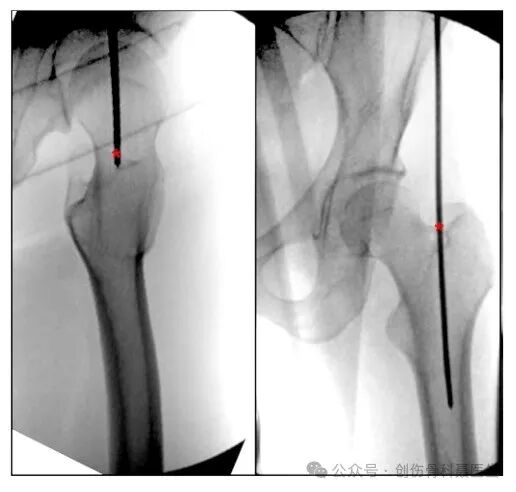

③股骨干顺行交锁髓内钉技术:

适应症:股骨粗隆下2cm,距膝关节9cm以上的各种类型骨折

体位:仰卧位或侧位

切口入点:❶大转子进针点:从大转子尖顶点的进针点,在正位中朝向髓腔的内侧,侧位中为大转子中心与股骨髓腔中心连线,大转子顶点进针点常用于肥胖患者,这种手术技术要求较低,与梨状窝进针点相比,它可以提供更少的手术时间和更低的并发症风险;

❷梨状窝进针点:大转子内侧的凹陷(股骨颈底部凹陷处)的闭孔外肌附着区